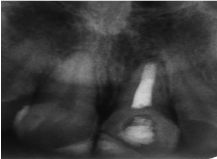

Clinical examination (figure 1a) revealed defective resin composite restoration on teeth #21 and #11. Tooth#21 showed an access cavity already done, with a clear discoloration. Sensitivity tests showed positive response only on tooth #11. The tooth #21 was tender to percussion with a physiological mobility. The periodontal state was unhealthy. The gingiva was inflamed with plaque and calculus on teeth. Periapical radiographic examination (figure 1b) showed an immature open apex of the tooth #21 with a radiolucent lesion in the apical area.

Figure 1b. A preoperative periapical radiograph of maxillary central region: observe open apex of tooth 21 with radiolucent area